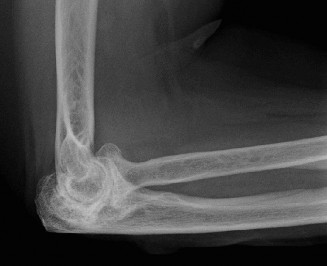

Understand common complications associated with performing surgery for scapulothoracic bursitis? CASE 33 A 42-year-old female presents to the office for follow up after sustaining a minimally displaced radial head fracture 3 months prior. She states she was initially treated in long-arm splint by the ER and did not follow up with an orthopaedic surgeon until now. Per her report, she removed the splint 4 weeks after the injury, but did not move her elbow due to pain. She now has no pain but is unable to reach that hand to her face or head. The remaining history is significant for previous ulnar nerve surgery for which she is unable to provide details. On physical examination, her upper extremity is normal except for limited flexion/extension, measured to be 80 to 50 degrees by goniometer. In addition, she has a well-healed surgical incision about the medial elbow, consistent with a previous surgery on her ulnar nerve. Her images are shown (Figs. 2–82 to 2–84).

Figure 2–82

Figure 2–83

Figure 2–84

What is the diagnosis?

- Early post-traumatic intrinsic joint contracture

- Late post-traumatic extrinsic joint contracture

- Late combined post-traumatic joint contracture

- Early combined post-traumatic joint contracture

Discussion

The correct answer is (A). Classification of post-traumatic elbow stiffness allows for better understanding of the disease and allows the clinician to treat the underlying cause of the joint contracture. Intrinsic causes include: any problem within the joint such as incongruency, loose bodies, or severe osteoarthritis. Extrinsic causes include capsular tightness, muscle contracture, heterotopic ossification, and skin contractures. Early is defined as within 6 months of the injury while late is considered to be greater than 6 months after the injury. Patients that present in the early time frame have a significantly better chance at having a good result both from nonoperative and operative treatment.